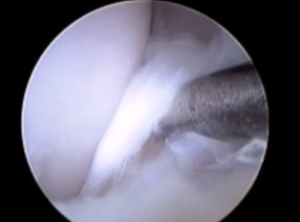

(動画)チワワ3kg 観察棒(probe)を用いて断裂した靭帯の触診。前十字靭帯完全断裂と滑膜炎が起きている。

前十字靭帯損傷の確定診断をする事が出来、同時に処置も可能です。また診断が困難とされている前十字靭帯の部分断裂に対しても正確に診断できることで、早期発見につながり術後経過にも影響します。関節鏡検査は、関節内を拡大して観察できることから、僅かな損傷も確実に発見でき、また関節の奥の方に存在する半月板の損傷の評価にも有用です。

膝関節周囲に小さな穴を2箇所あけて、関節鏡(スコープ)を関節内に挿入し、直接、拡大して検査することができます。一般的にスコープは、2.4〜2.7ミリのサイズを使います。

関節鏡画像

(右)チワワ 2kg

前十字靭帯の完全断裂 靭帯の断端が切れて”ささくれ”ていました。左横に関節内の調べるための器具がみえています